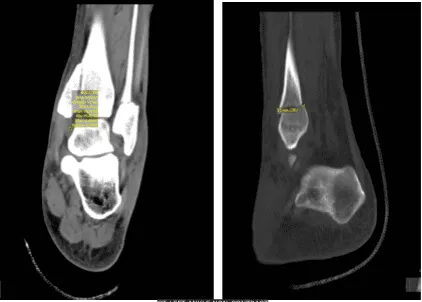

TAC – Tobillo izquierdo sin contraste

Para una revisión más detallada de la condición del tobillo, acordamos realizar un TAC. El resultado mostró fractura trimalleolar cicatrizada tras ORIF, con placa y tornillos en el peroné, y el maléolo medial con una deformidad leve con un paso de 1 mm en la superficie articular en el plafond tibial medial.

Deformidad leve en el margen anterior de la palma tibial. No hay nuevas fracturas. Hemos decidido realizar fisioterapia formal así como un programa de ejercicios en casa para la rehabilitación de la rodilla. Los pacientes seguían regularmente una visita a la consulta cada 3-4 semanas. El paciente se recuperó bien tras la cirugía y continuó la fisioterapia.